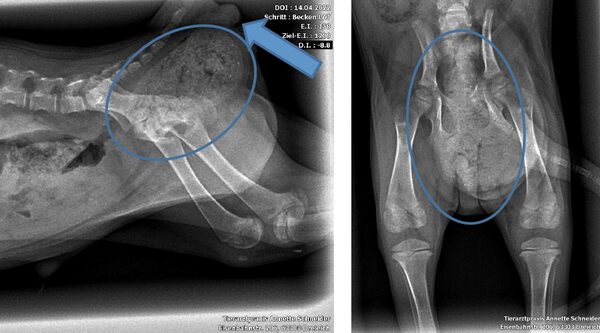

Chui, ein 13jähriger großer Mischlingsrüde, kam zu uns, da er Beschwerden beim Laufen hatte.

Bei der Untersuchung fiel auf, dass sein Bauch sehr hart und aufgetrieben war.

Die Röntgenuntersuchung zeigte eine riesige Masse in seinem Bauch.

Mittels Ultraschall konnte die Organzugehörigkeit nicht sicher festgestellt werden.

Trotz Chuis hohem Alter entschied sich sein Frauchen für eine gewagte Operation.

Es zeigte sich, dass es sich um einen 5 kg schweren Tumor der Milz handelte. Dieser konnte erfolgreich im Ganzen entfernt werden.

Der histopathologische Befund ergab ein Hämatom, also eine Einblutung. Dieser Befund ist nur mit Vorsicht Anlass zur Erleichterung, da es sich bei diesem Fall mit Sicherheit um einen Tumor handelte. Dies ist für den Pathologen aber nicht immer sicher feststellbar.